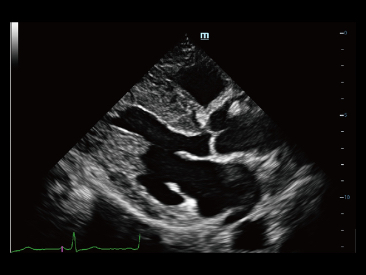

Mindray? ??? ??? ?? ??? ???? ??? ?? ??? ??? ????? ??? ????. ?? ???? ZONE Sonography? ??? ???? ?? Resona 7? ??? ZST+ ???? ?? ?? ? ?? ??? ????? ?? ??? ??? ??? ? ?? ????.

?? Resona 7? ???? ??? ?? ???? ??? ??? ???? ??? ?? ???? V Flow? ?? CNS ??? ?? 3D ??? ???? ?? ???? ?? ??? ?? ?? ?? ??? ??????. ???? ??? ??? ?? ?? ??? ??? ?? ?? ??? ??? Resona 7? ??? ???? ???? ??? ??? ??? ????.